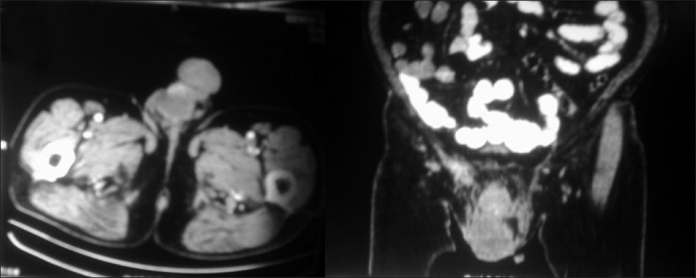

On examination, performance status according to Eastern Cooperative Oncological Group[2] , Scoring was 2; all the vital parameters were normal. Local examination revealed a 10×15 cm tense, firm, and tender swelling involving the right scrotum. On palpation, the swelling was not reducible. One could get above the swelling. Testicular sensation was lost on the left side. The opposite side testis was normal. A computed tomography scan of the abdomen and pelvis showed heterogeneous soft tissue right testicular mass, which was measuring 10×6×5 cm in size with some evidence of necrosis within the right testicles and there were right inguinal lymph nodes [Figure 1]. At this time, the differential diagnosis was infected hydrocele/pyocele or organized hematoma was entertained. Preoperatively complete blood count, serum biochemistry, and thyroid function tests were normal; viral serology (retroviral and Epstein bar virus) was negative. Beta human chorionic gonadotropin and alpha-fetoprotein values were normal. Hence, he was taken up for surgery. Per-operatively, he seemed to have tumor testes infiltrating the scrotal wall. Therefore, high orchidectomy with excision of hemiscrotum was done. The opinions from four different pathologists were sought. The histopathology gave a differential diagnosis of testicular tumor with scrotal sac wall infiltration/diffuse large cell non-Hodgkins immunoblastic/anaplastic lymphoma; poorly differentiated carcinoma in favor of embryonal carcinoma; poorly differentiated malignant tumor most consistent with plasmacytoma. Immunohistochemistry showed Vimentin, CD30, CD 138 Lambda chains positive, increased Ki 67, EMA, CD79a, S100P positive, in favor of anaplastic plasmacytoma [Figures 2 ((aa–k) and 3 ((aa–i)]. EBER, cyclin D1, MiB1, and CD 56 were not done due to logistic reasons. In the meanwhile, workup for MM was done, which showed normal serum electrophoresis and β2 microglobulin level. Urine was negative for Bence Jones protein. Tc99m Bone scan and bone marrow reports were normal. After a lapse of 2 months due to the diagnostic dilemma, treatment was started for plasmacytoma with daily tab – thalidomide 100 mg weekly tab, dexamethasone 40 mg daily tab, melphalan 5 mg twice daily for 5 days. The patient has completed six cycles of chemotherapy and is in remission.

| Fig. 1 (a)Testicular plasmacytoma CT scan axial section preoperative picture showing right testicular mass. b: Testicular plasmacytoma CT scan coronal section preoperative picture showing right testicular mass